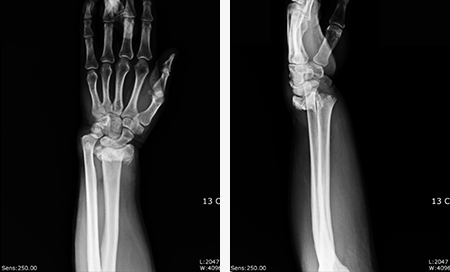

손목 골절

겨울철 낙상사고에서 가장 흔히 발생하는 골절 중 하나입니다.

수술 전